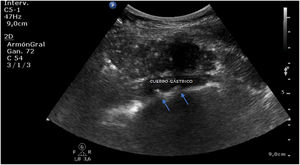

A las pocas horas, en el control sonográfico, se puede apreciar la endoprótesis (fig. 1) con sus pinzas (flechas en la figura 2) en la región del cuerpo gástrico, en la ventana esplenorrenal. A través de una endoscopia se recoloca la prótesis hasta su correcta ubicación. En seguimiento por ecografía, se comprueba la desaparición del dispositivo en el cuerpo del estómago (fig. 3).